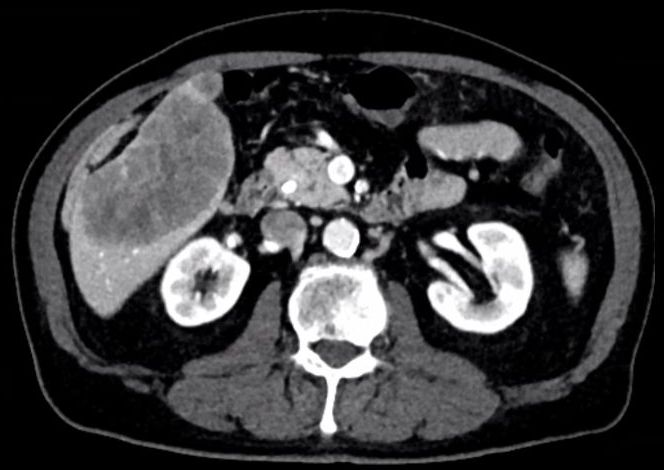

| Diagnostik | 70-jähriger Mann mit unklaren Oberbauchbeschwerden rechts. Klinisch vergrößerte Leber tastbar. Metastasen in BWK 8, Lunge und abdominalen sowie mediastinalen Lymphknoten. Leberbiopsie: Invasives Adenokarzinom, intrahepatisches Cholangiokarzinom. Das CT zeigt eine über 10 cm große Raumforderung im rechten Leberlappen.  | ||